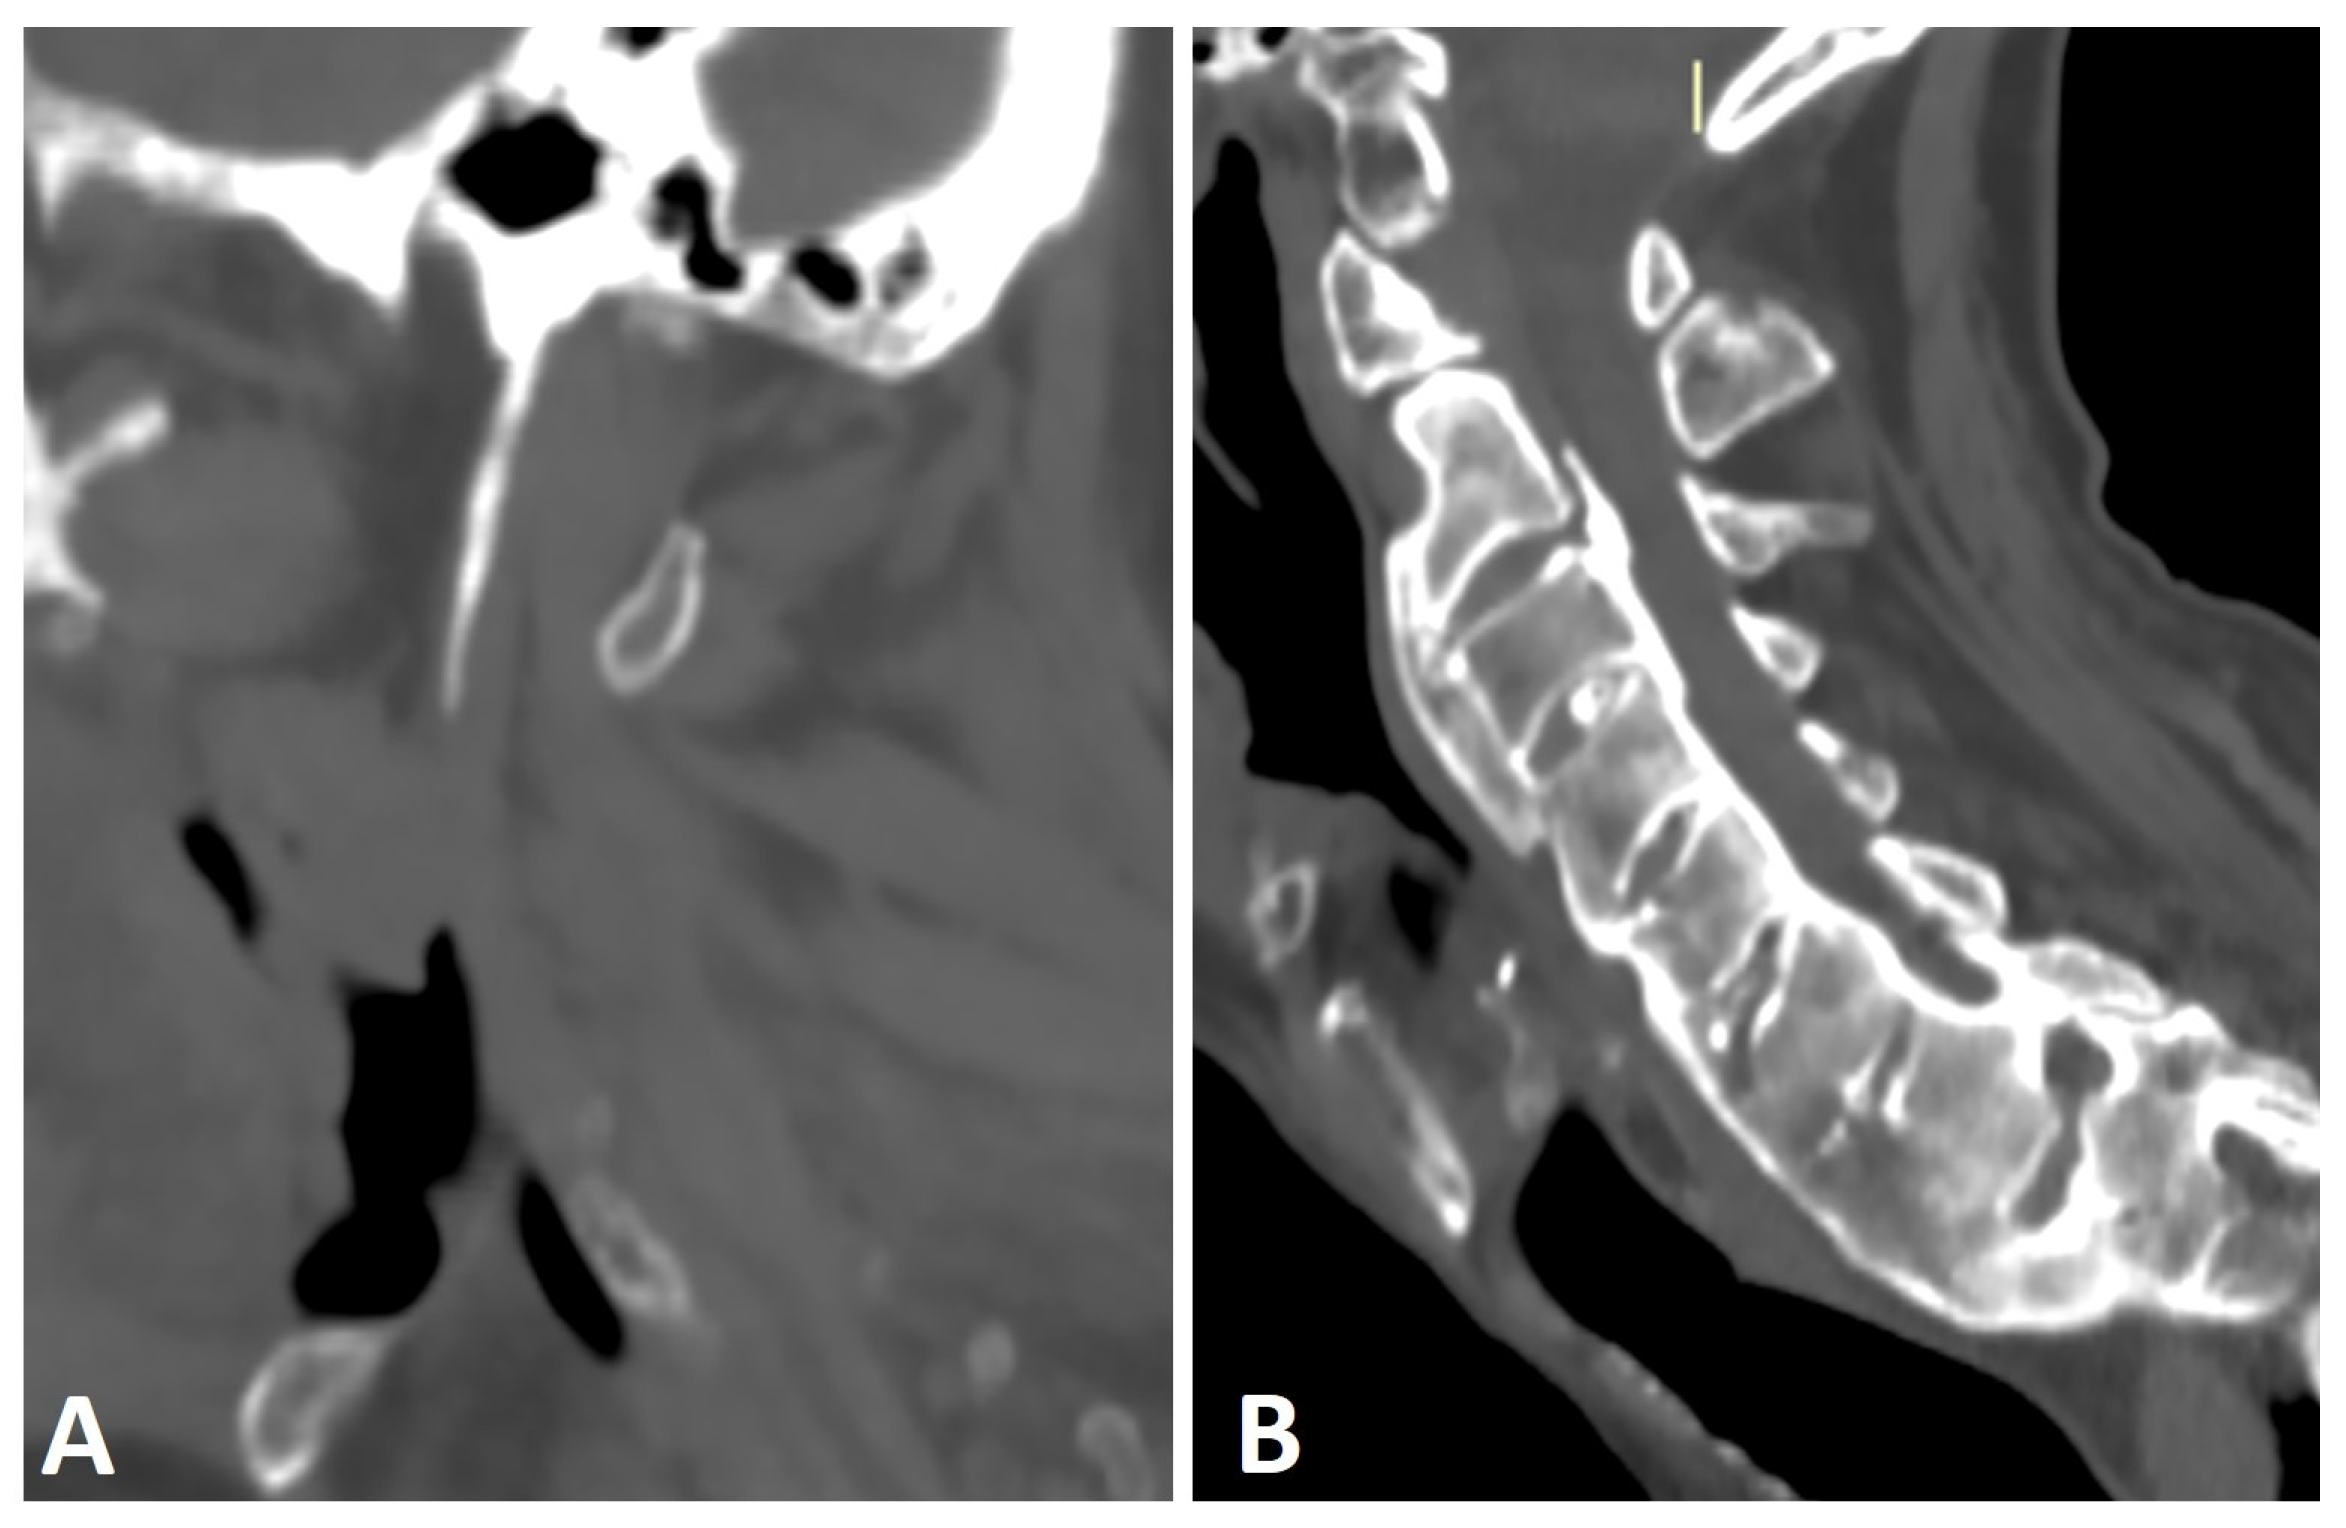

Another phenomenon known to coexist with DISH is an elongation of the styloid process, which results from entheseal calcification and ossification of the stylohyoid ligament (Figure 4A) [38,39,40,41]. In rare cases, this elongation has been reported to cause craniofacial or cervical pain, termed Eagle syndrome [42]. In a study comparing the length of the styloid process, as measured by CT, between subjects with DISH (as per Resnick and Niwayama criteria), subjects with AS (as per modified New York criteria), and healthy controls, the average lengths of the styloid process in DISH and AS were similar but significantly greater than that of the controls [41]. Moreover, significantly more subjects with AS (30%) and DISH (25%) had an elongated styloid process (>3 cm) than the control group [41]. However, no correlation was seen between the presence of characteristic bone bridging osteophytes in the cervical spine of DISH subjects and an elongated styloid process. Enthesopathy, which is a common feature in both DISH and AS, distinguishes these patients from healthy subjects by causing styloid process elongation. Enthesopathy in AS patients is thought to be of an inflammatory nature [43]. Although enthesopathy in DISH has been classically attributed to mechanical or degenerative causes, it has been suggested that subclinical inflammation is also a cause of cervical enthesopathy in DISH [7,16].

Figure 4.

Sagittal CT reconstructions of the cervical spine of two patients with thoracic DISH (not shown). (A) The elongated styloid process results from calcification and ossification of the stylohyoid ligament. (B) Flowing osteophytes characteristic of DISH accompanied by OPLL.

Ossified posterior longitudinal ligament (OPLL) is a hyperostotic condition that may lead to spinal canal stenosis and, potentially, neurological manifestations of varying degrees [44]. OPLL is a distinct entity that may appear without accompanying pathologies, with an incidence of up to 4% [45,46]. It has been reported to be associated with DISH, AS, and diabetes mellitus [45,46], with a concomitance rate of 57.14% for cervical OPLL accompanying DISH (Figure 4B) [47]. Both DISH and OPLL are primarily observed in elderly males and have a reported association with low glucose tolerance and obesity [47]. A shared local inflammatory pathogenesis has been suggested as the basis of both entities; however, this hypothesis needs further corroboration [48].